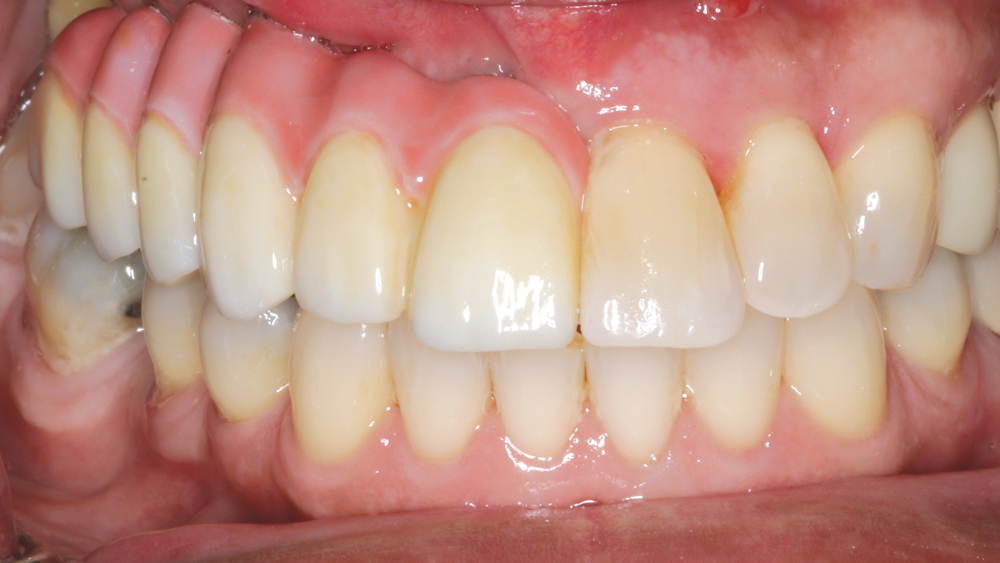

Esthetics and occlusion can be challenging in these types of cases. Restoring half an arch and trying to mirror the contralateral soft tissue and dentition with proper contours and shade requires patience and resolve. The lab provided a PMMA try-in prosthesis, which I evaluated with Weldon. The try-in allowed us to easily resolve any discrepancies with the prosthetic design and develop ideal occlusion. Once Weldon agreed on the esthetics, the PMMA provisional was returned to the lab and duplicated in BruxZir Solid Zirconia. This extra step eliminates excessive chairside adjustments upon seating of the final prosthesis.

The PMMA try-in prosthesis ... allowed any necessary adjustments to easily be made to the prosthetic design prior to milling the final BruxZir restoration.

BruxZir Solid Zirconia has proven to be extremely strong yet compatible with opposing natural dentition; the material exhibits minimal wear on the opposing enamel. Its color and shading are extremely natural in appearance, and I have no concerns about chipping or cracking of the material over time. The final seating of the prosthesis was straightforward, and I have confidence that the material is a long-lasting solution. Weldon was thrilled with the final restoration, as we were able to surpass his expectations and provide him with a fixed, functional, esthetic result.